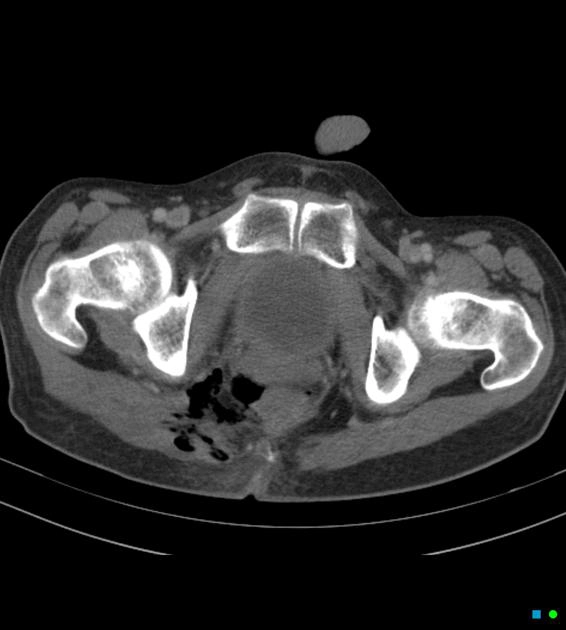

• Bìu và thừng tinh

• Bệnh lý viêm nhiễm

Hoại tử tầng sinh môn Fournier (Fournier gangrene)

16/03/2026